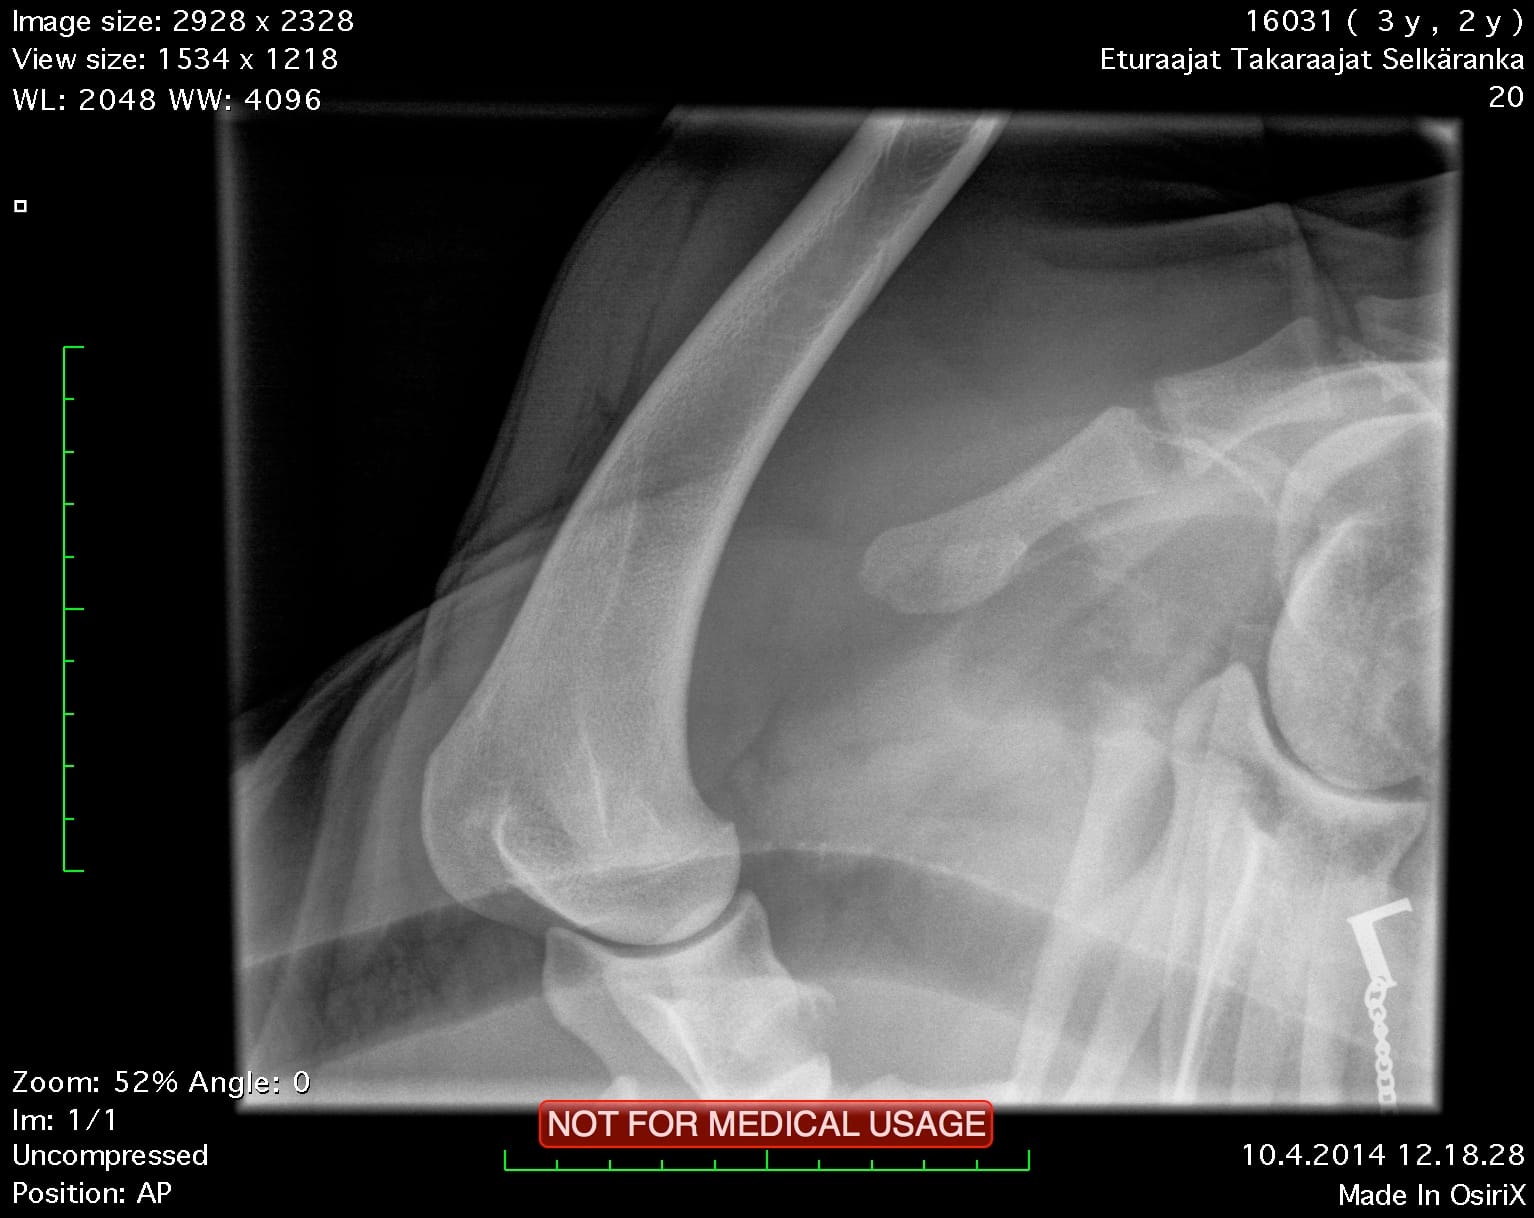

| Elbows: | 0/0 | |

| Shoulders: | clear | |